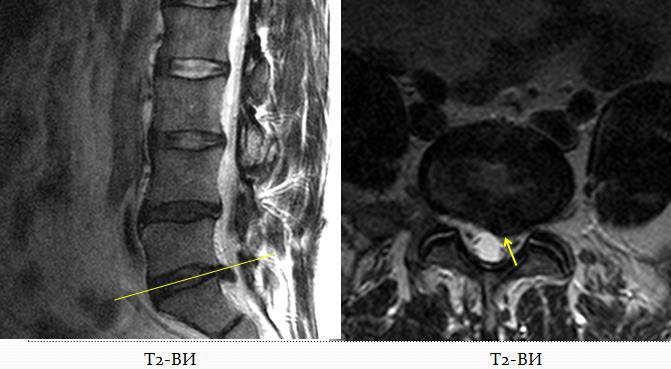

Дорзальная парамедианная левосторонняя грыжа диска L5-S1 с двусторонним сужением просветов корешковых каналов: